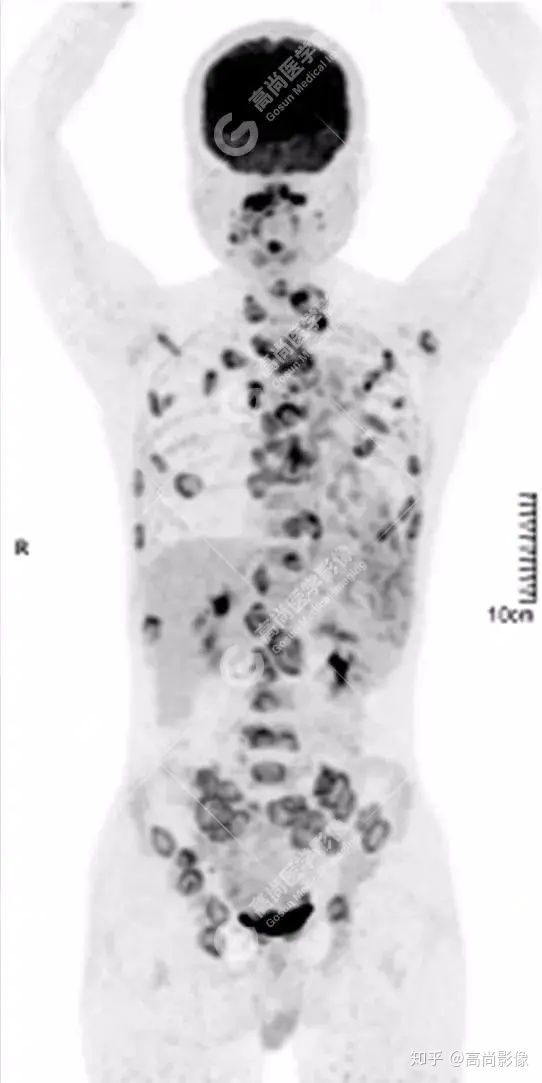

PET/CT 全身圖

脊柱多發(fā)椎體及附件骨質(zhì)破壞,代謝不均性增高

全身多處骨質(zhì)破壞,代謝不均性增高

全身多發(fā)高代謝腫大淋巴結(jié),中央代謝缺損

左肺上葉尖后段及下葉背段多發(fā)簇狀斑點(diǎn)狀高代謝灶

左側(cè)胸膜結(jié)節(jié)樣增厚,代謝不同程度增高

【PET/CT提示】雙肺、左側(cè)胸膜多發(fā)結(jié)節(jié)影,全身多處骨質(zhì)破壞,全身多發(fā)淋巴結(jié)腫大,代謝攝取不均勻性增高。